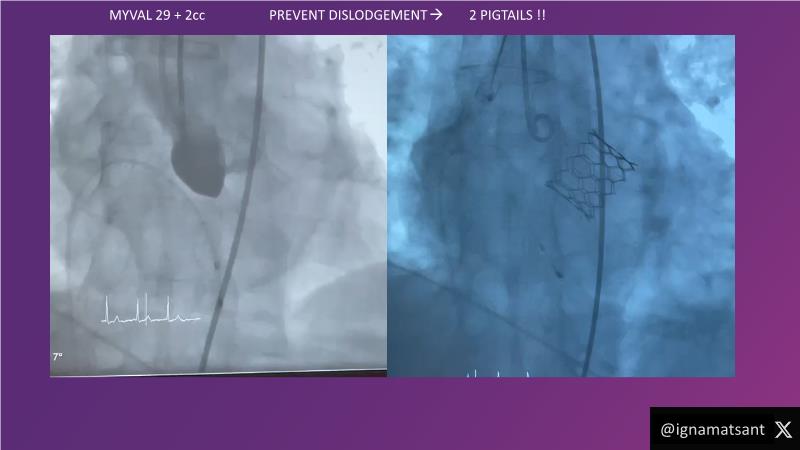

This session is a valuable resource for grasping innovative strategies in handling bifurcation and extended diffuse lesions through dedicated stenting solutions. Explore insights into the advanced Myval next-generation THV technology, unveiling its distinctive features, procedural advantages, and clinical outcomes across a diverse patient pool. Gain understanding into the CorAlign technique, ensuring accurate commissural and coronary alignment while maintaining coronary access. Additionally, delve into the techniques for precise sizing, positioning, and deploying of Myval THV.

- To understand the technique of precise sizing, positioning and deployment of Myval THV